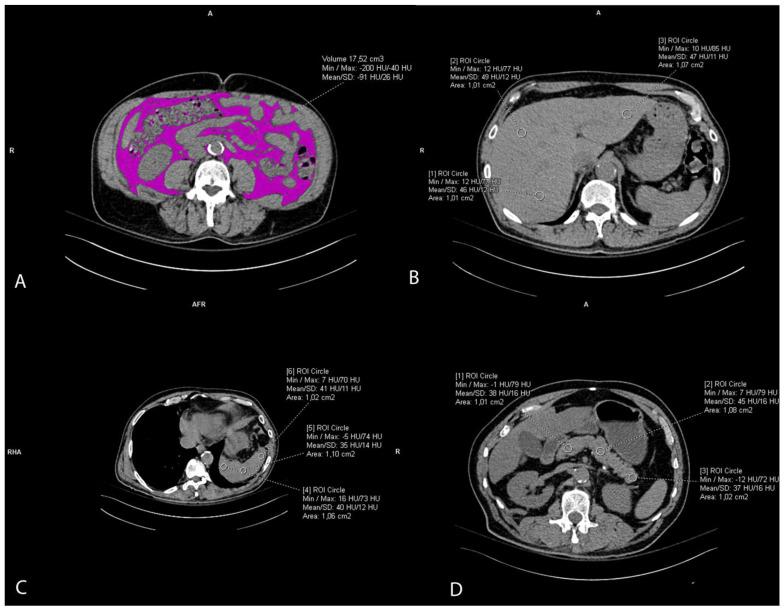

The vascular risk associated with obesity is particularly associated with visceral adiposity, but recent studies suggest that ectopic fat might contribute to the increased risk of atherosclerotic cardiovascular disease. Our study aimed to explore the connection between arterial calcification of the aorta and renal arteries with visceral and ectopic fat deposits, including liver, pancreatic, and renal sinus fat. Retrospective analysis of thoracoabdominal multi-slice computed tomography (MSCT) scans of 302 patients included measurements of calcification volumes of thoracic and abdominal aorta, and of both renal arteries. On the same scans, the visceral fat volume, liver-to-spleen ratio, pancreatic-to-spleen ratio, and both renal sinus fat areas were retrieved. Logistic regression showed the left kidney sinus fat area to be the most strongly associated with calcifications in the aorta and both renal arteries (coef. from 0.578 to 0.913, < 0.05). The visceral fat positively predicted aortic calcification (coef. = 0.462, = 0.008), and on the contrary, the pancreatic fat accumulation even showed protective effects on thoracic and abdominal aorta calcification (coef. = -0.611 and -0.761, < 0.001, respectively). The results suggest that ectopic fat locations differently impact the calcification of arteries, which should be further explored.